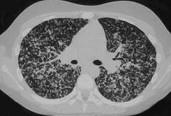

问题 女性,19岁,低热,盗汗,乏力,咳嗽1月余,CT检查如图,请选出最可能的诊断 ( )

选项 A.间质性肺炎 B.弥漫型肺癌 C.粟粒型肺结核 D.硅沉着病 E.大叶性肺炎

答案 C